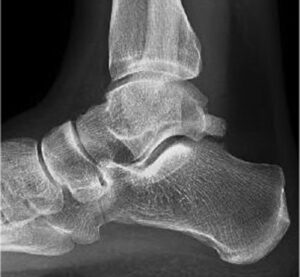

Caso clínico

En la imagen mostramos una radiografía lateral en carga de un paciente con limitación a la flexión dorsal del tobillo. El paciente padece pinzamiento de tobillo, choque o impingement. Se produce debido a la colisión de las superficies óseas de astrágalo y tibia en la zona que señalamos.

Habitualmente los pacientes con esta patología refieren dolor cuando están caminando y cargando todo el peso en el pie. Este momento coincide con el 2º rocker del paso, cuando se debe producir un avance de la tibia sobre el astrágalo sin ningún tipo de limitación.